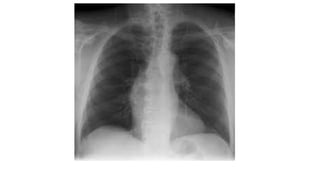

Chest x -ray findings

• Cardiomegaly RT.side.

• Normal left heart

• RA enlargement.

• RV enlargement.

• Full pulmonary conus.

• Increased pulmonary vascular

marking, Plethoric lung fields